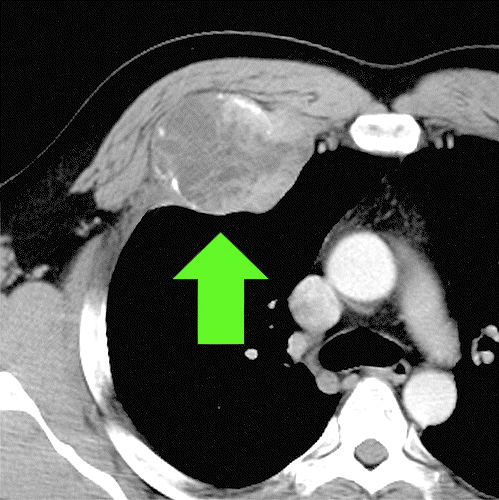

At Saint John’s Health Center, we will perform an X-ray to see if there is an abnormality. If there is an abnormality visible on the X-ray, we will do a CT scan (computed tomography) or MRI (magnetic resonance imaging) scan to gain additional information about the chest wall abnormality, such as size and location. These scans provide additional detail including soft tissue structures.

- CT scans may be used to identify inflammation in areas of the chest.

- CT scan of the chest

Diagnosis of rib fractures is achieved via X-Ray, CT scan, or MRI, which can also look at the organs and soft tissues around the ribs to detect damage to these areas. Most non-displaced fractured ribs heal without surgery in one to two months and are treated with non-surgical care that ranges from aggressive pain management to proper ventilation. For patients with displaced fractures, flail segments, or high narcotic requirements surgical treatment with rib plating may be required along with aggressive pain management and proper ventilation.